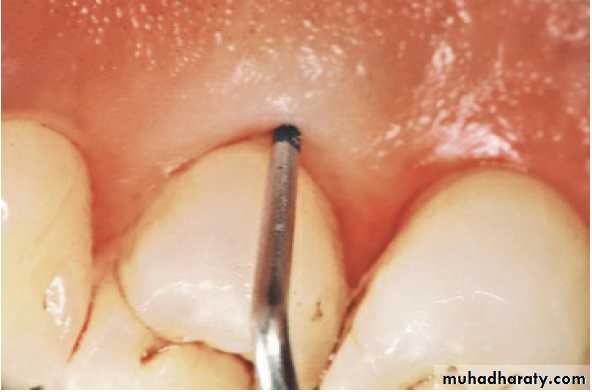

• The only reliable method of locating periodontal

pockets and determining their extent is careful

probing of the gingival margin along each tooth

surface.

Periodontal Probes: Periodontal probes are used to measure the depth of pockets and to determine their configuration. The typical probe is a tapered,

rod like instrument calibrated in millimeters, with a blunt, rounded

tip